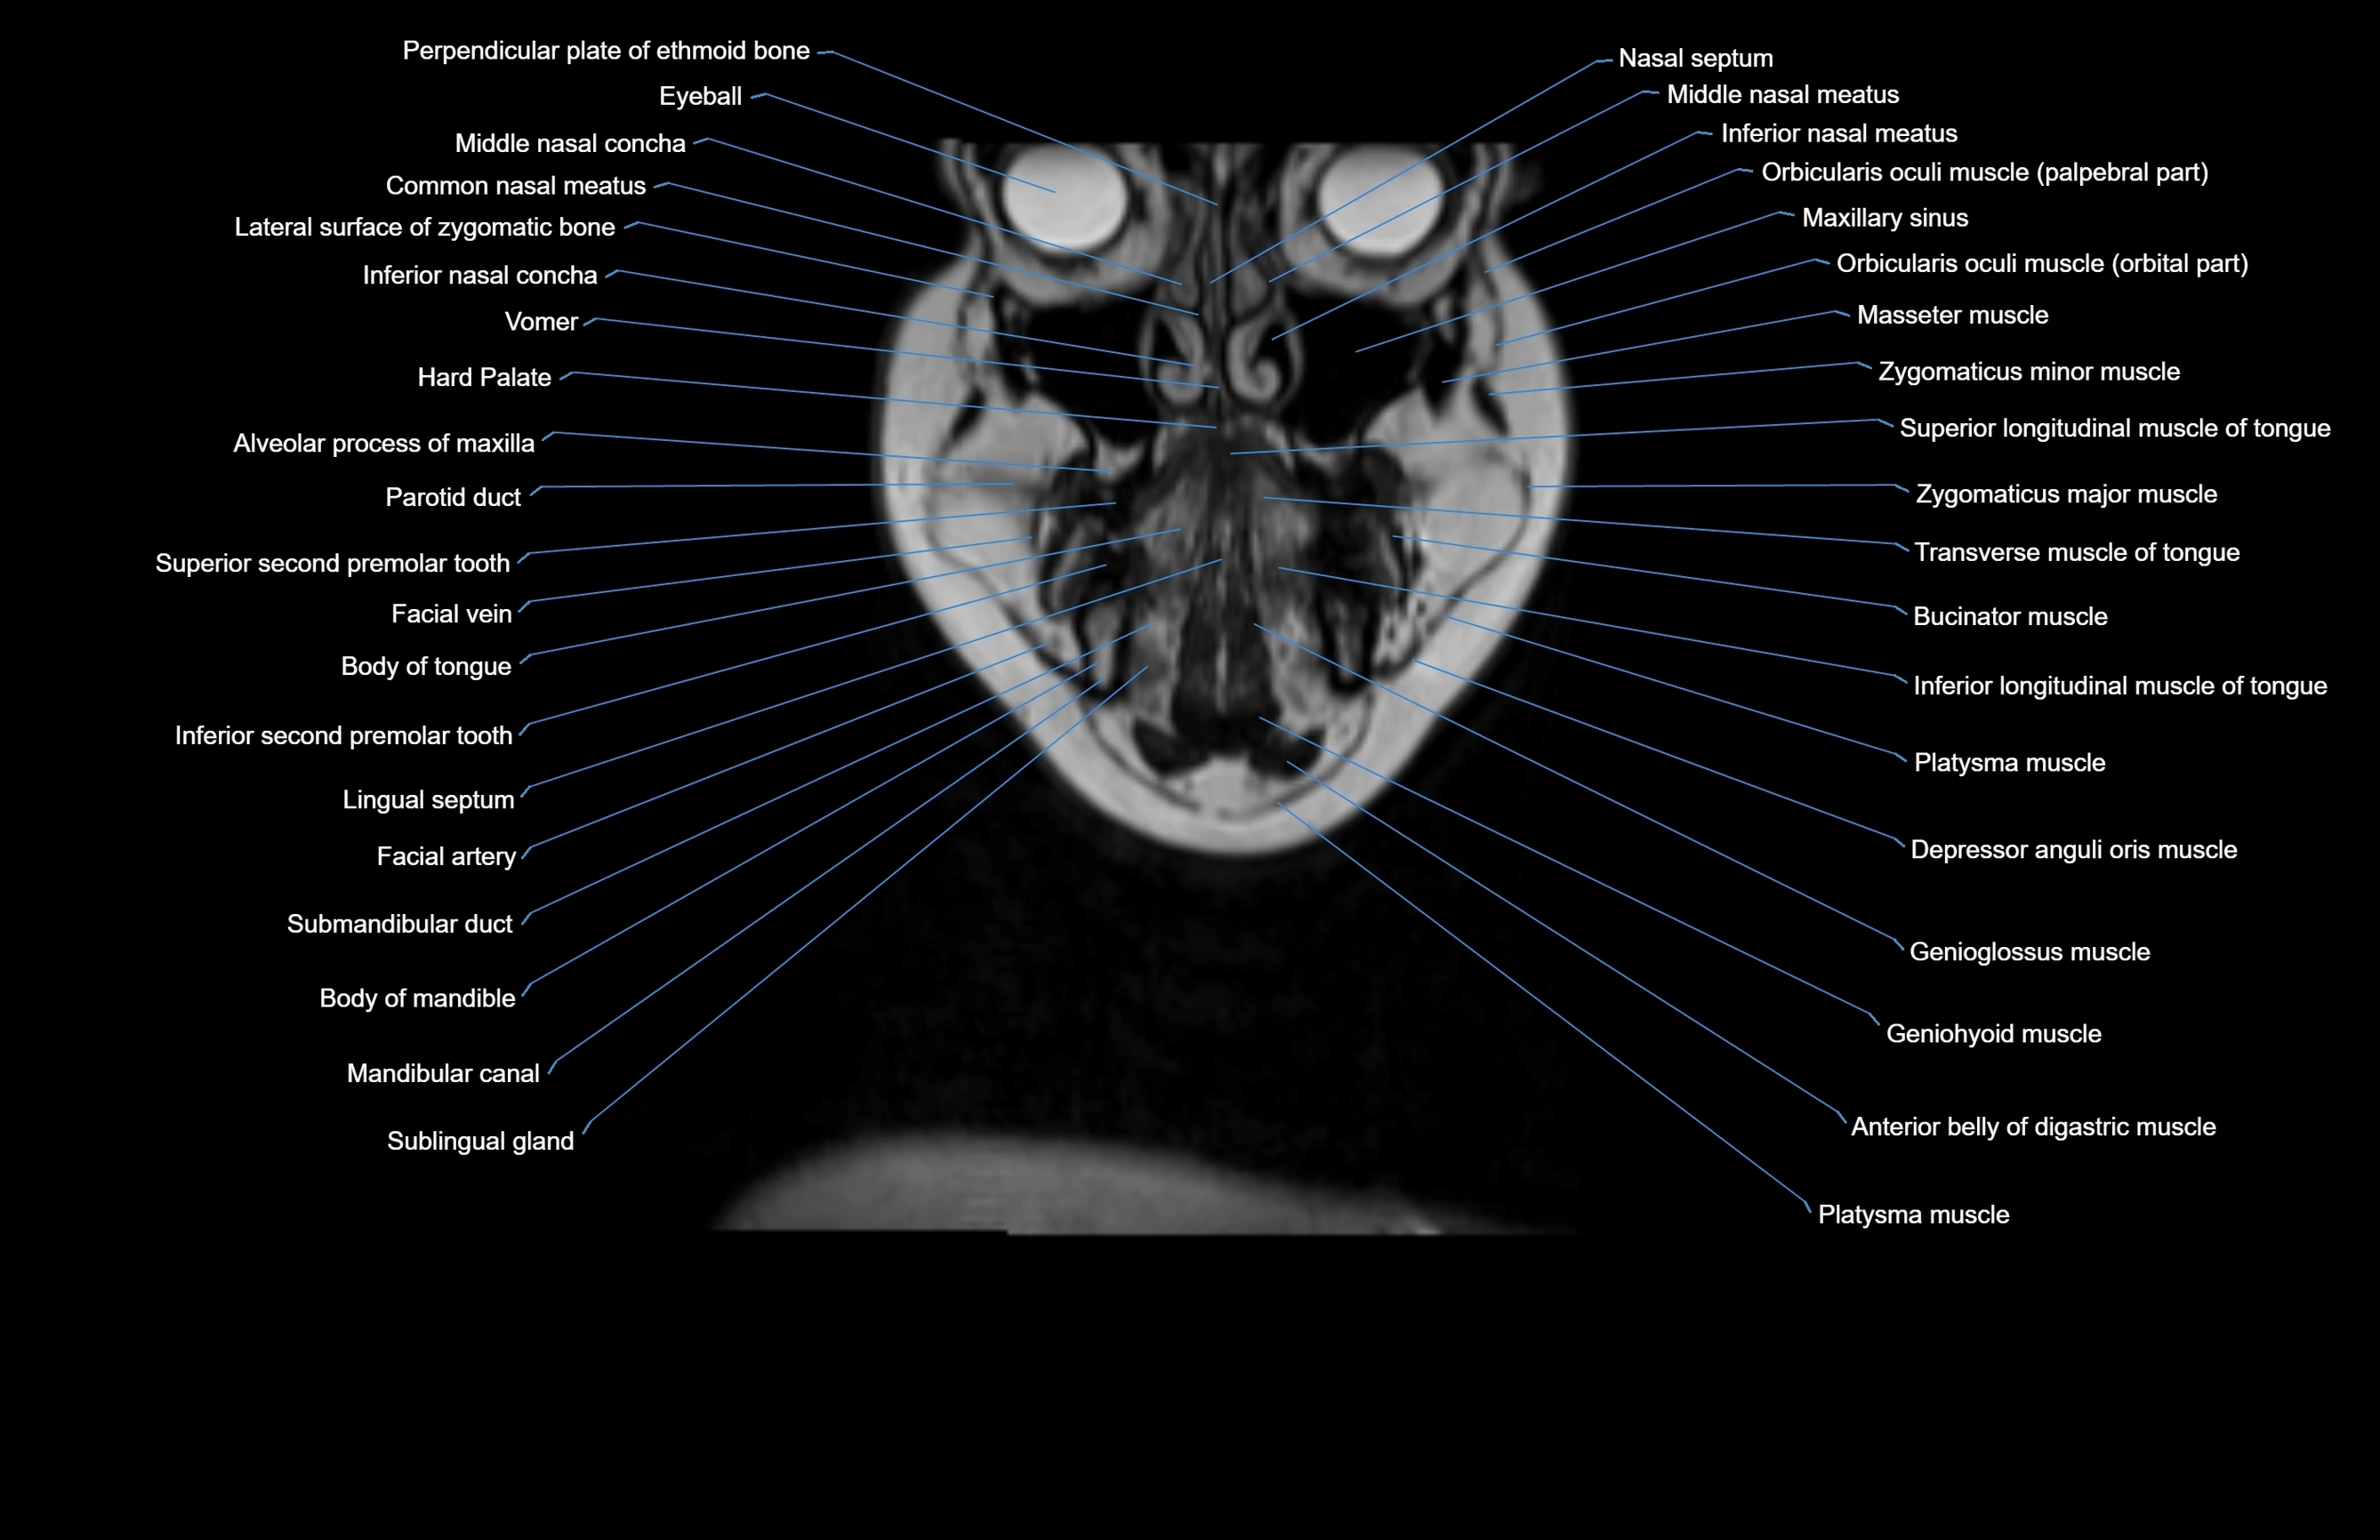

- Nasal septum

- Middle nasal concha

- Common nasal meatus

- Inferior nasal concha

- Eyeball

- Maxillary sinus

- Facial artery

- Facial vein

- Parotid duct

- Sublingual gland

- Submandibular duct

- Body of mandible

- Mandibular canal

- Depressor anguli oris muscle

- Genioglossus muscle

- Inferior longitudinal muscle of tongue

- Transverse muscle of tongue

- Buccinator muscle

- Platysma muscle